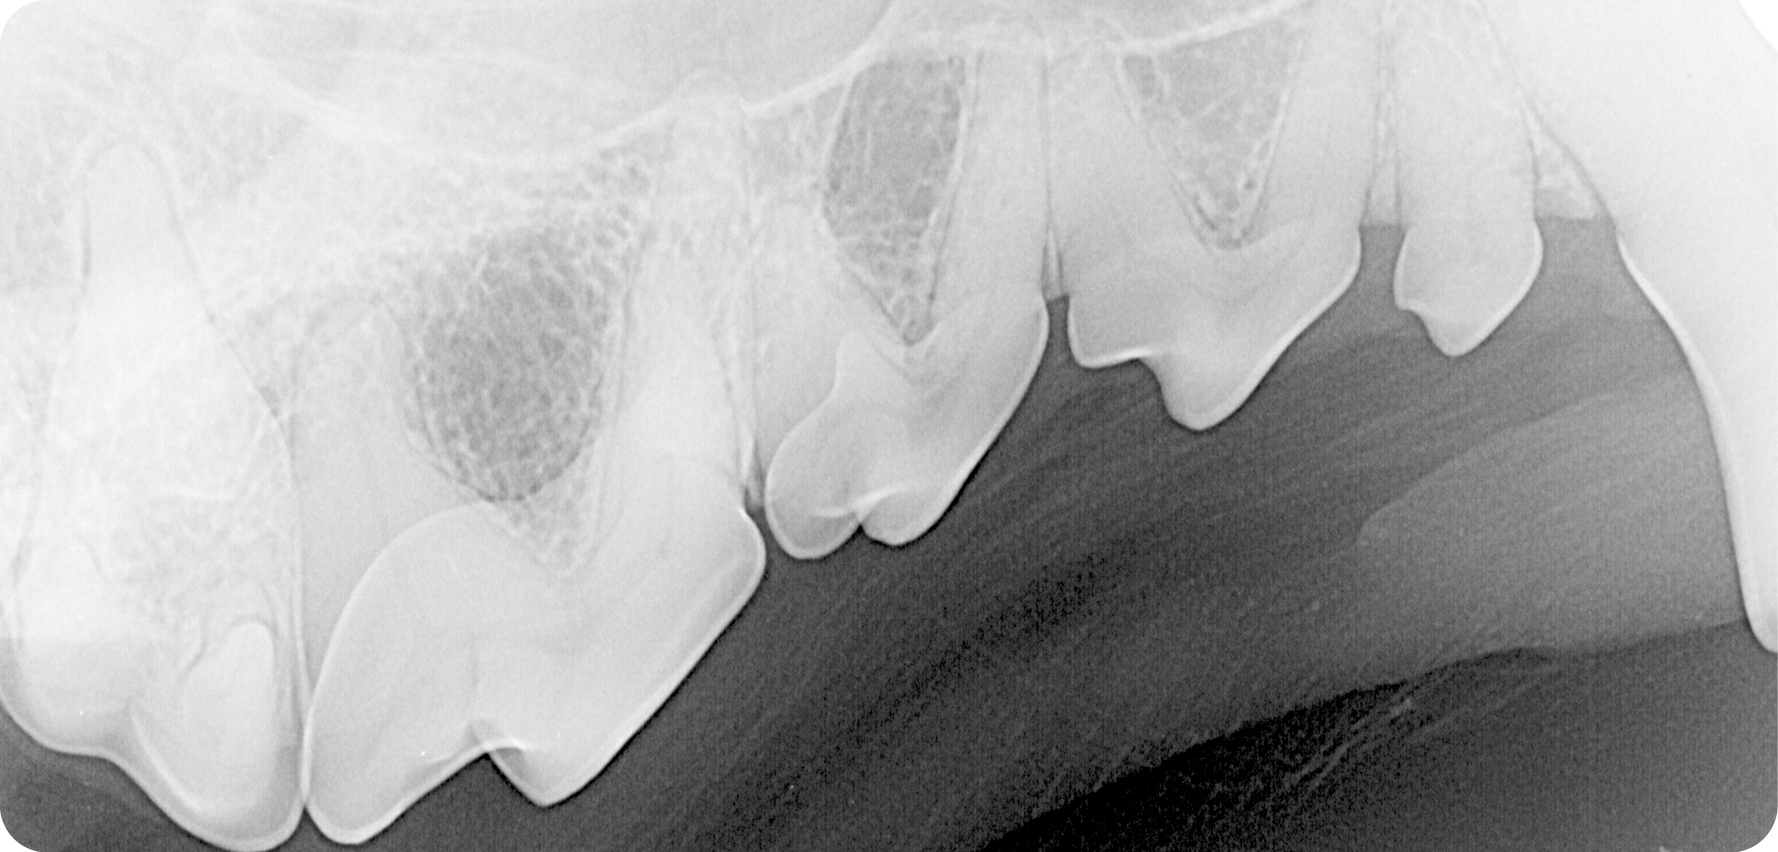

Röntgenbeispiel Katze: Die Aufnahme einer Katze (Abb. 1) zeigt eine überzählige Wurzel des zweiten Prämolaren (⭐️) im Oberkiefer rechts. Darüber hinaus wird auch ein zusätzlich angelegter Zahn im Bereich des zweiten Prämolaren

sichtbar (➡️).